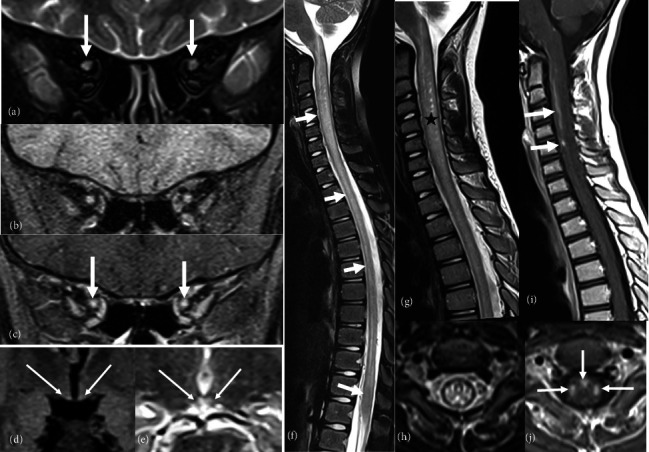

Biotinidase deficiency is a rare treatable metabolic disorder caused by biallelic mutations in the BTD gene. In the absence of neonatal screening and treatment, affected children develop typically optic atrophy, hypotonia, early onset seizures, developmental delay, and cutaneous manifestations. Some patients may have atypical presentations mimicking a demyelinating disorder of the central nervous system. We report on the first genetically confirmed Tunisian patient with biotinidase deficiency who presented initially with cutaneous manifestations misdiagnosed as dermatophytosis and subsequently with an opticospinal syndrome leading to the diagnosis of seronegative neuromyelitis optica spectrum disorder that was dramatically improved under biotin. We carry on a review of the literature of the previously reported pediatric cases with an opticospinal syndrome revealing biotinidase deficiency.

Abstract Image